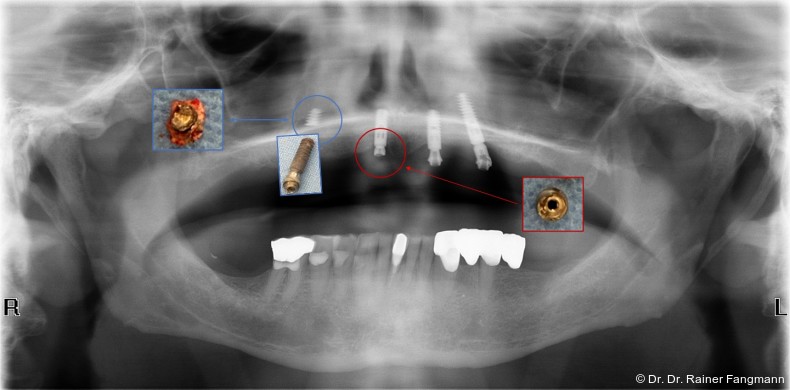

Im ersten Beispiel erschien die Patientin nach prothetischerRehabilitation mit einem gegossenen Steg mit Schmerzen am rechten äußeren Implantat. Nach Lösung dieser Schraube kam es zur Besserung der Beschwerden. Der gegossene Steg wies kein Passive-Fit auf.

Im zweiten Beispiel lockerten sich die Basisaufbauten bei der Stegeinprobe. Die Abutments wurden refixiert und die prothetische Arbeit fortgesetzt. Nach einem Jahr Tragezeit kam es zum Implantatverlust und Implantatbruch bei den refixierten Abutments. Es wurden Implantate nachgesetzt und das Konzept der Stegversorgung verlassen. Es erfolgte eine Umstellung auf eine teleskopierende Arbeit sowohl im Oberkiefer und prophylaktisch auch im Unterkiefer, obwohl es in der S3-Leitlinie keine Empfehlung für diese Versorgungsform gibt. Bei der Refixierung der Abutments kam es zu Vernachlässigung der Passive-Fit-Anforderung. Bei einem indexfreien Abutment ist die 360° Drehbarkeit gegeben. Das lässt eine freie prothetische Gestaltbarkeit zu. Bei Abutmentlockerung ist dann der Steg neu anzufertigen, da die Passive-Fit-Passung der Suprastruktur nicht mehr möglich ist. Bei indexierten Abutments ist durch die chirurgische Implantatinsertion die prothetische Ausrichtung vorgegeben. Die indexfreien Abutments geben dem Prothetiker mehr Freiheiten.

Im dritten Beispiel erfolgte die Abformung nicht auf Abutmentniveau, sondern auf Implantatniveau. In diesem Beispiel wurden die Abutments mit dem CAD/CAM-Steglaborseits verklebt. Um die Eingliederung in der Mundhöhle zu ermöglichen, wurden die Abutments am Verbindungselement zum Implantat beschliffen. Das wirdseitens des Implantatherstellers nicht empfohlen. In einem vierten Beispiel kam es acht Wochen nach der prothetischen Versorgung zum Implantatbruch. Das Implantat zeigt an der Fraktur einen deutlichen Versatz. Der Steg zeigte auf den restlichen Implantaten eine spürbare und sichtbare Spannung. Hier liegt der Fehler sicherlich in der Abformung. Zumindest wurde die Spannung bei Insertion des Stegs auf die Implantatabutments vom Prothetiker nicht registriert. In einem fünften Beispiel kam es nach vier Jahren zur Implantat- und Abutmentfraktur. Hier ist das Geschehen auf den gleichen Mechanismus wie im Beispiel Vier zurückzuführen. Es zeigt sich eindeutig ein Anwenderfehler. Im Nachgang kann davon ausgegangen werden, dass der Steg von links nach rechts verschraubt und so die Spannung aufgebaut wurde, die für das Frakturgeschehen ursächlich ist.